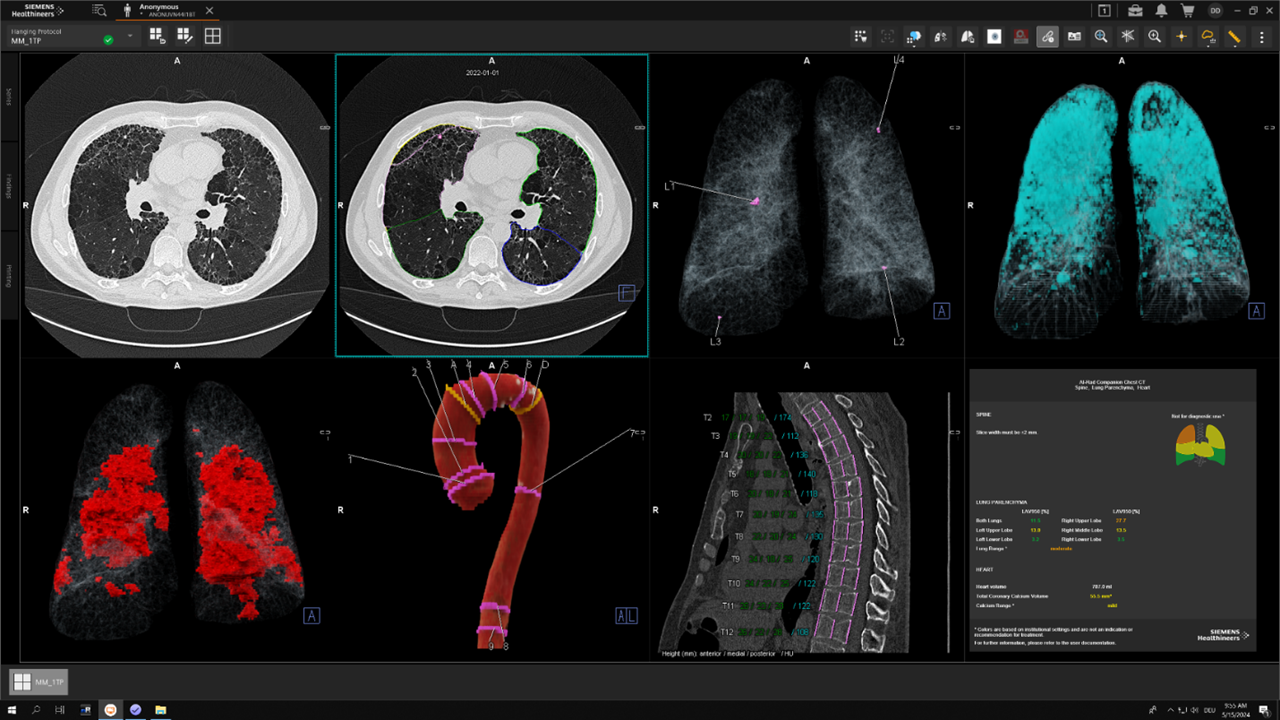

She demonstrated the Siemens Healthineers’ AI-Rad Companion Chest CT, showcasing its segmentation of nodules, lung parenchyma, fibrosis, and even the aorta. But she also cautioned:

- “Bias in training data still exists.”

- “Not all findings flagged are real—AI has a learning curve, just like we do.”

- “Use it to confirm, not to diagnose blindly.”